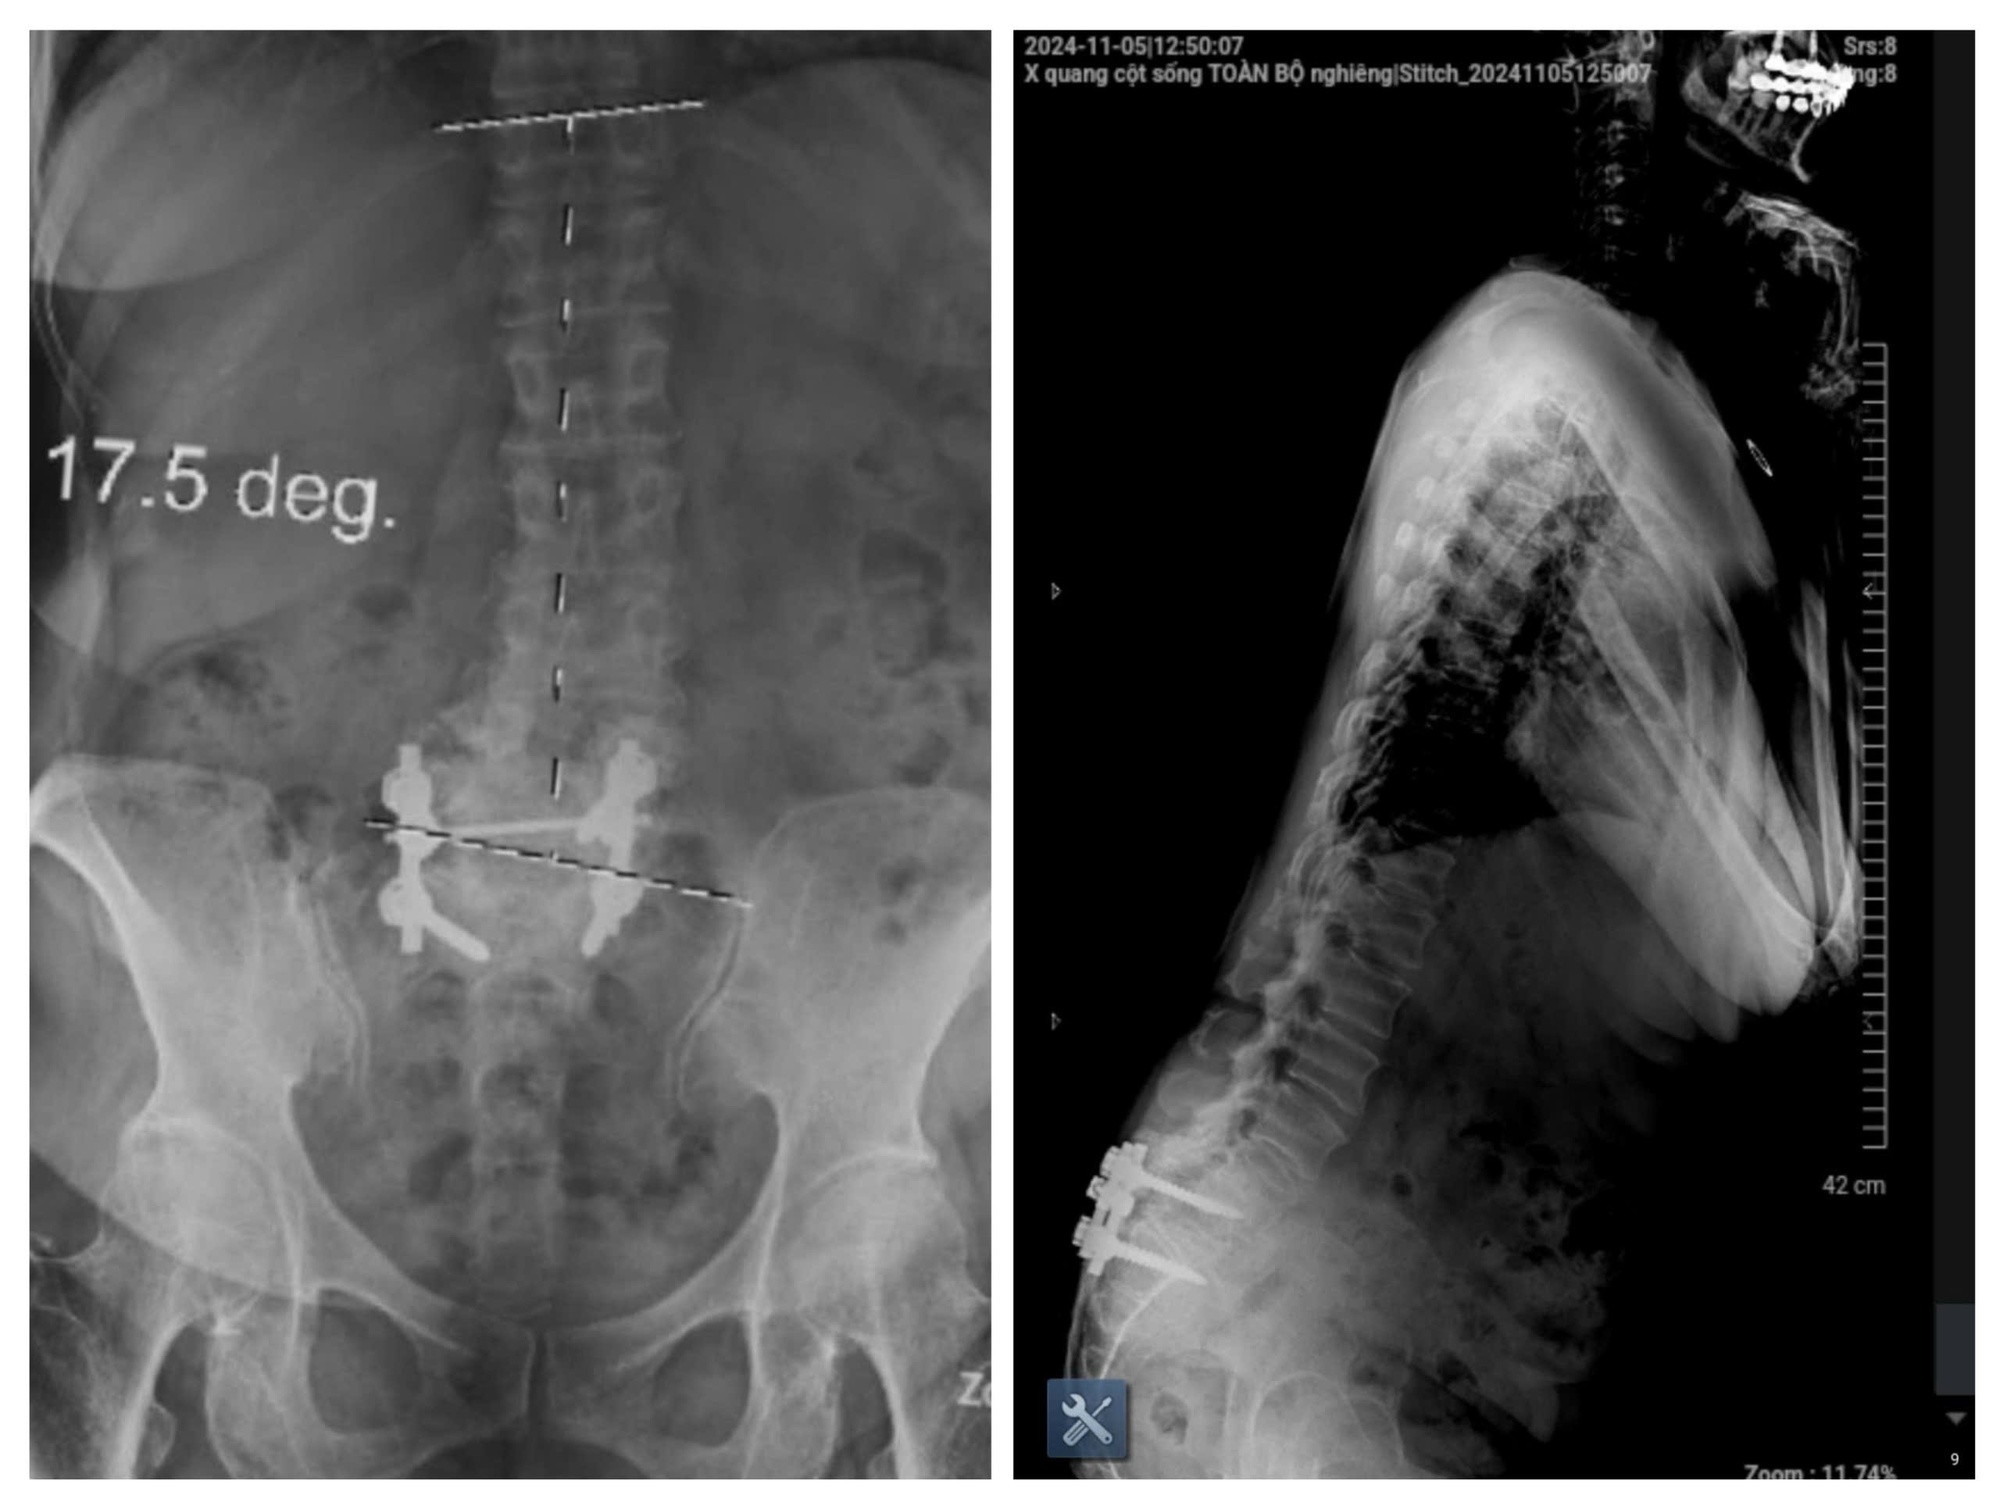

Hình ảnh phim chụp của bệnh nhân vào tháng 11/2024. (Ảnh: BSCC)

Theo BS Cao Thanh Phong, hình ảnh cận lâm sàng cho thấy:

- Hở eo và trượt đốt sống L4 ra trước độ II

- Thoát vị đĩa đệm L4/L5 ra sau, có phần di trú

- Hẹp ống sống nặng, đường kính trước - sau <7mm

- Hẹp ngách bên, lỗ tiếp hợp, chèn ép toàn bộ rễ thần kinh ngang mức L4 và L5

Không dừng lại ở đó, bệnh nhân còn có phình đĩa đệm tại nhiều tầng khác như L2/L3, L3/L4 và L5/S1, gây chèn ép bao màng cứng và hẹp ống sống mức độ nhẹ.